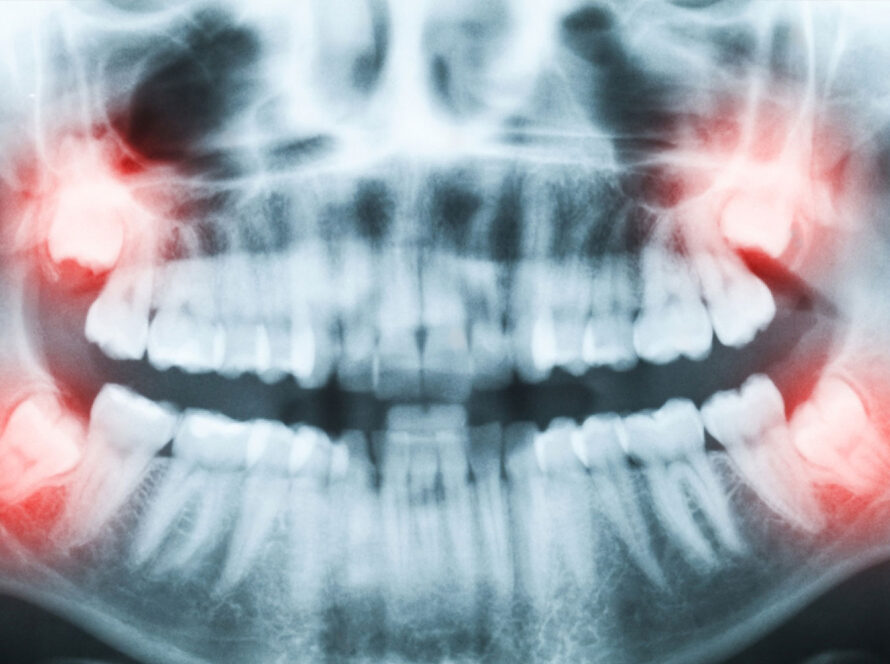

HOW MUCH DO YOU KNOW ABOUT GUM DISEASE?

According to national surveys, more than half of American adults have periodontitis, which is advanced gum disease. That shocking statistic works out to more than sixty million people! At Southern York Smile Care in Shrewsbury, it has us wondering: how much do you know about gum disease?